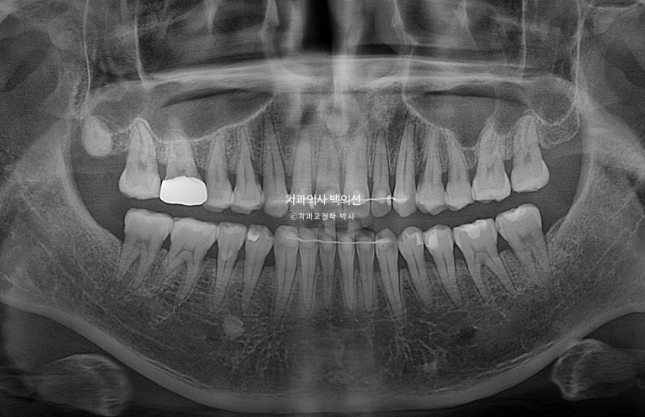

25.03

교정 후 파노라마 엑스레이상 치근흡수는 없으며 치근형행도는 좋습니다.